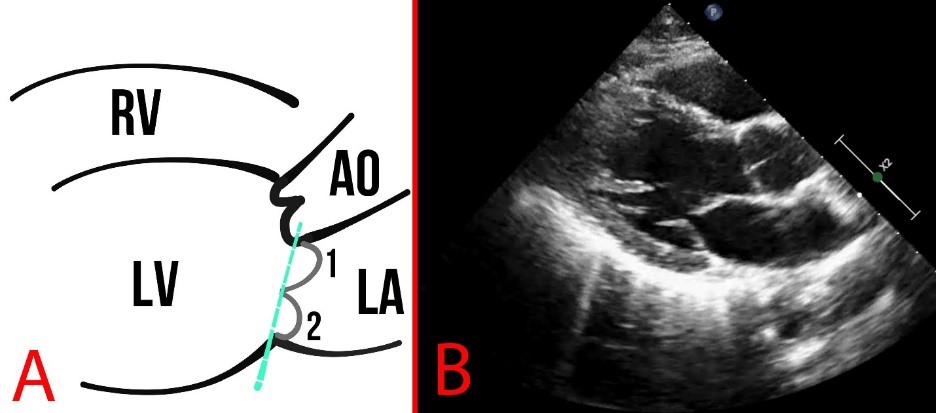

The structure and function of the MV leaflets are evaluated polypositionally using different modes, such as M-mode, B-mode, and Color Doppler mode. Normally, the mitral annulus has a curved shape and a saddle-shaped bend in the sagittal plane (Fig. 3).

Fig. 3. Schematic presentation (A) and echocardiography (B) of normal findings. (A) The numbers 1 and 2 show the mitral valve flaps, the line (3) shows the mitral annulus, and the arrow indicates the coaptation zone. LA, left atrium.